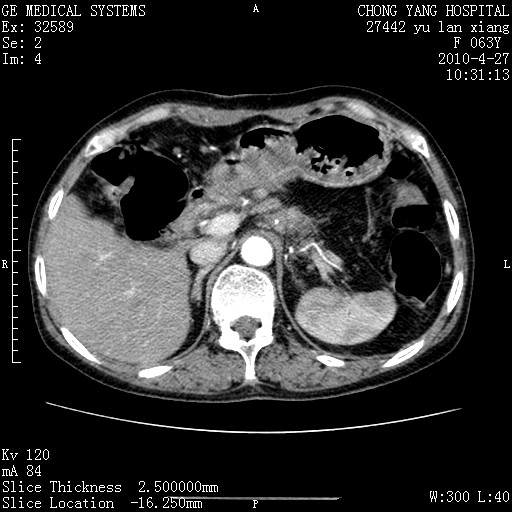

标题: CT26066:F63Y 上腹正中压痛半月,CA199:7400u/ml,MR示胰腺炎伴 [打印本页]

胰腺癌侵犯腹腔动脉干-分支、胃壁、左侧膈肌伴胰周及腹膜后淋巴结转移、胆囊切除术后。

胰腺癌侵犯腹腔动脉干-分支、胃壁、左侧膈肌伴胰周及腹膜后淋巴结转移、胆囊未显影。